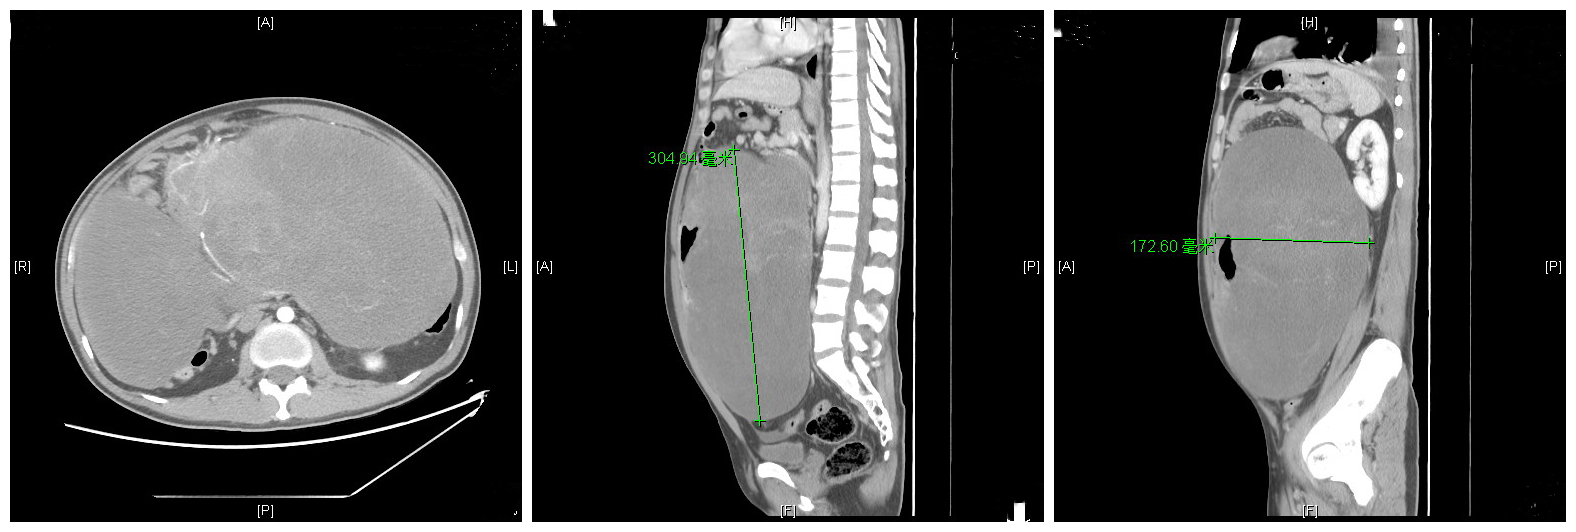

全腹部CT: 腹腔内见巨大肿块,大小约29.1cm×14.7cm×29.3cm